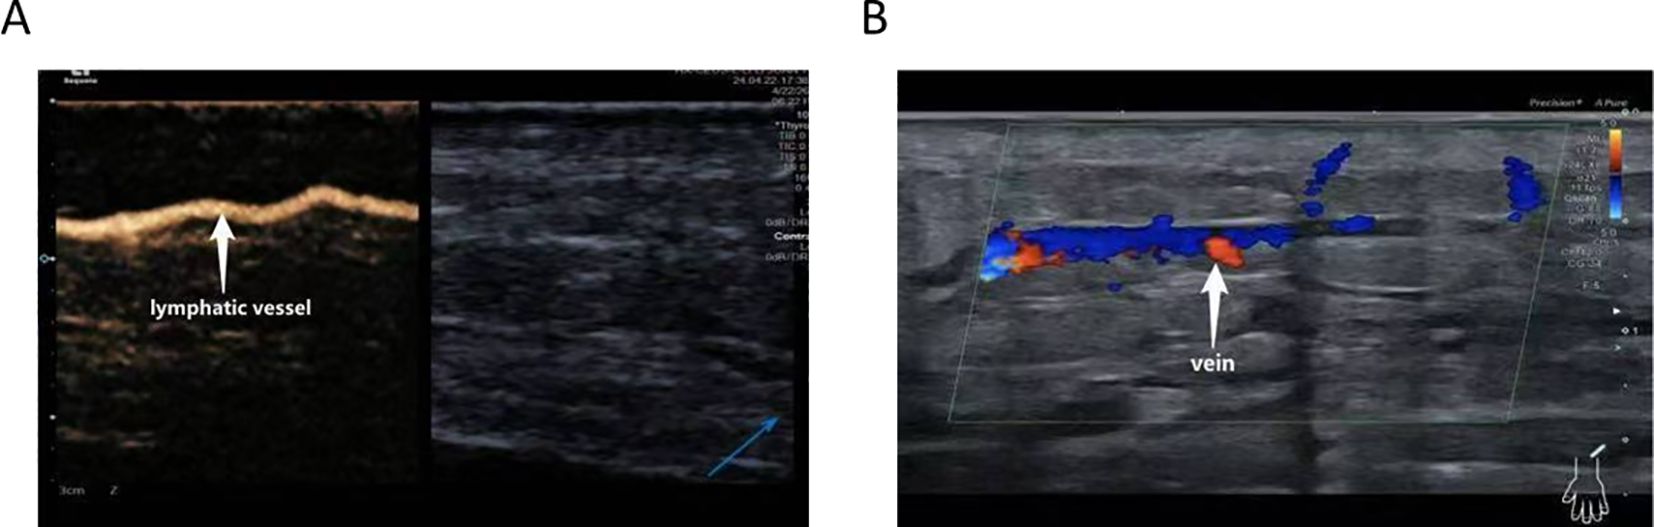

CEUS was employed to precisely localize functional lymphatic vessels and target recipient veins (Figure 2) one day prior to surgery, followed by precise skin marking for intraoperative localization (Figure 3). On April 23, 2024, the patient underwent right upper limb lymphaticovenous anastomosis under general anesthesia. The surgical procedure entailed the following steps: (1) the patient was placed in the supine position with the affected limb abducted at 90°, followed by endotracheal intubation and standard sterile preparation; (2) an incision was made at the site of preoperatively identified lymphatic vessels and recipient veins near lymph node basins, with careful dissection to isolate the vessels; (3) end-to-end anastomosis of lymphatic vessels to veins was performed using 11–0 nylon sutures under microscopic magnification (Figure 4);(4) meticulous hemostasis was ensured, and the subcutaneous tissue and skin were closed in layers with running sutures; (5) postoperative management included compression bandaging with elastic wraps, skin care, and rehabilitation exercises as part of comprehensive decongestive therapy.

Ultrasound images labeled A and B. Image A shows a highlighted lymphatic vessel, indicated by an arrow. Image B displays a vein with colored Doppler flow represented in blue and red, also indicated by an arrow.

Figure 2. CEUS–assisted localization of functional lymphatic vessels (A) and target veins adjacent to lymphatic vessels (B).